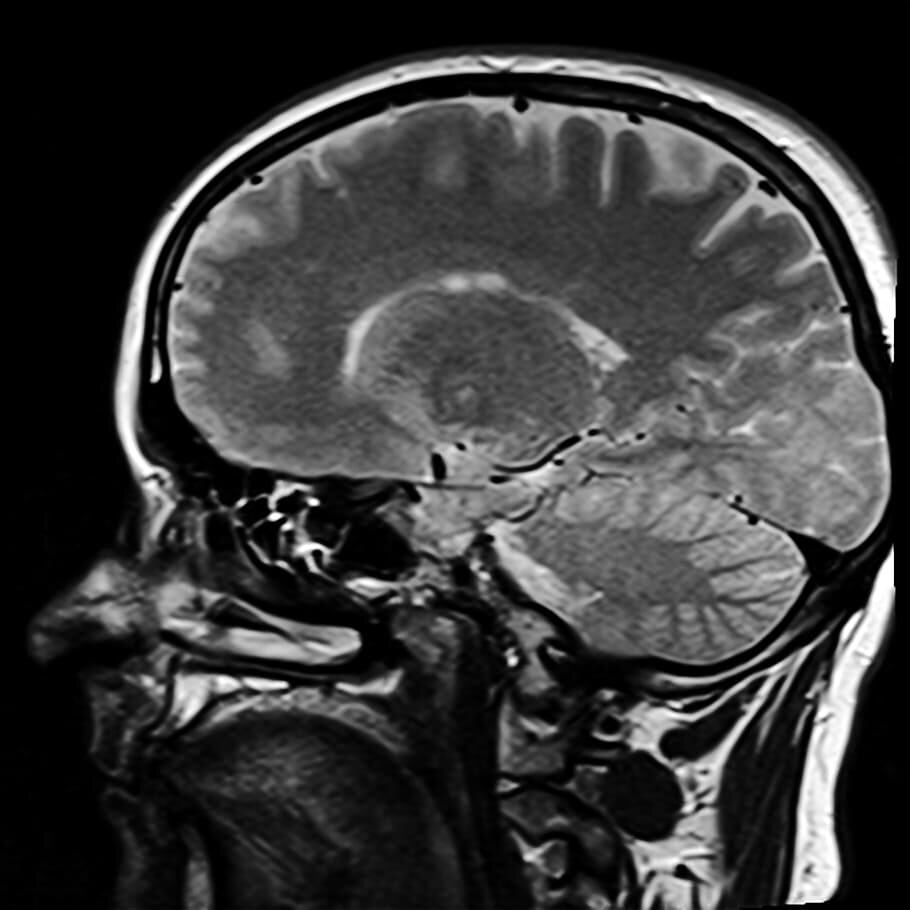

- Не существует безопасного количества алкоголя для мозга. Чем больше алкоголя потребляется, тем меньше объем мозга потребителя, - сказала Сазонова.